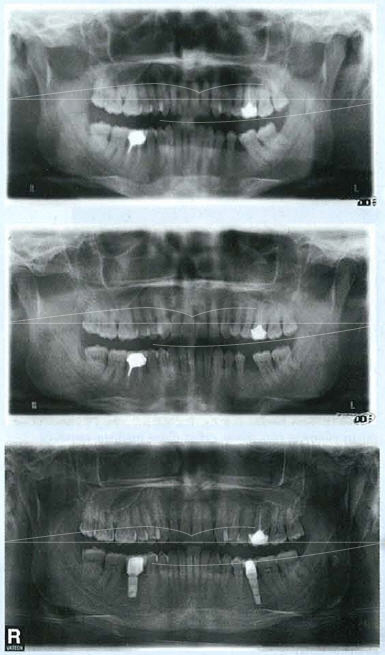

CAS CLINIQUE

Notre patient nous est adressé pour redresser l'axe de la 36 afin de poser un implant. Après lui avoir fait un bilan ODF complet, nous lui proposons différentes solutions du redressement molaire à l'alignement des arcades pour améliorer le contexte parodontal jusqu'au traitement d'orthodontie complet en recréant une classe 1 dentaire, le patient choisit l'alignement et l'amélioration globale en même temps que le redressement dentaire.

Photos du clin check

le clincheck est un set-up "wax up informatique". qui permet de visualiser les objectifs de traitement. C'est une image 3D statique de début et de fin associé à une image dynamique pour adapter la vitesse et le lieu de déplacement entre chaque aligneur®. Ce modèle est la base de la fabrication de toute la série d'aligneurs® à l'avance. Sur notre patient, les photos du clincheck avant et après de l'arcade supérieure et inférieure montrent l'alignement des deux arcades et l'ouverture de l'espace implantaire.